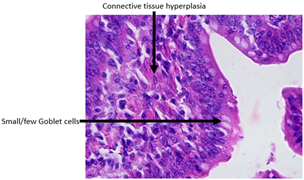

| Observations | Picture 40× | Picture 400× | |

|---|---|---|---|

| Samples from the CTL group | Inflammatory cellular infiltrates in the mucosa (with the participation of heterophils) Single mitotic figures in crypt epithelial cells Connective tissue hyperplasia |  |  |

| |||

| SNCE group | Scant infiltration of inflammatory cells in the mucosa (with the participation of heterophils) and the formation of individual lymphatic nodules Numerous goblet cells/heavily filled with mucus Vesicular nuclei of intestinal crypt epithelial cells; numerous mitotic figures |  |  |

|